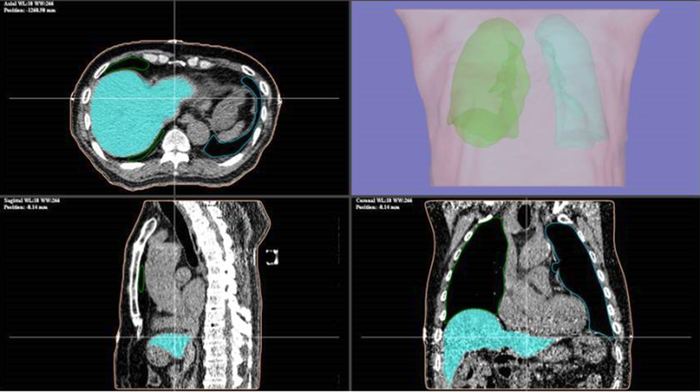

深層学習による臓器自動抽出

ワンクリックで胸腹部臓器の3D領域を自動抽出。体表・肺・肝臓・腎臓・脊柱管など 7種類以上の臓器に対応。放射線治療計画の大幅な効率化を実現。